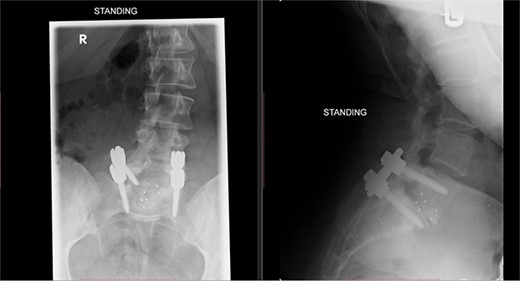

Postoperatively, the patient developed severe radiculopathy down the left leg and required opiates. The patient could not move the left leg and was unable to mobilize. X-rays showed the implants were in position (Fig. 3), but the information from a fresh MRI scan was limited due to metal artefact (Fig. 4). With ongoing, unrelenting pain, she was returned to theatre on the fourth postoperative date, and the wound was re-explored. Intraoperatively, no dural tear was identified, the nerve roots were free, and the screws appeared in position. She was then discharged home after ten nights in hospital, instead of the standard three nights that would be common practice.

Postoperative MRI of the lumbar spine performed in January 2017. Interference from the metallic pedicular screws limited the scans clarity.